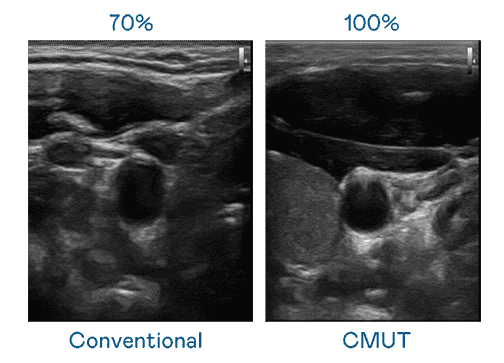

CMUT 技术是一种用电容式微机电元件来产生超音波讯号的技术。。。。与传统 PZT 压电式技术相比,,,CMUT 频宽增加 30%,,更宽频的超音波讯号让影像解析度大幅提升,,是实现高影像品质医疗超音波扫描、、、促进精准医疗发展的关键技术。。。

超音波影像的解析度高低,,首先取决于探头能发出的讯号频宽。。。尊龙z6 CMUT 可提供高清晰的超音波讯号,,,,提供高频宽、、、、高灵敏度、、、影像纹理细节更高的超音波影像,,,,协助医护人员缩短影像判读时间及利用精准的医疗影像进行诊断。。